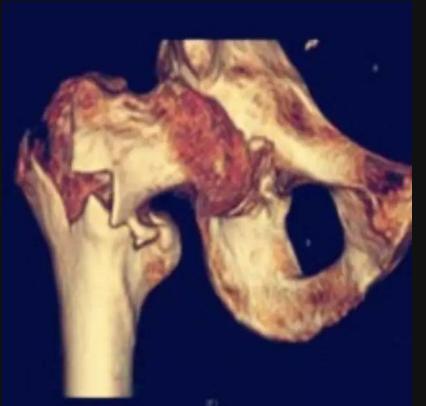

髋关节这里,有两个位置经常发生骨折,一个叫做股骨颈骨折,一个叫做粗隆间骨折。如果是股骨颈骨折,而这两个不同位置的骨折,又分别有四种常见术式:

粗隆间骨折——

老年人骨质疏松严重造成腰骨折,髋部骨折包括哪些骨折